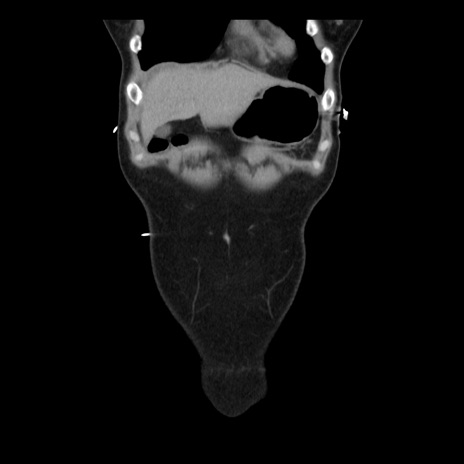

症例10(冠状断像)

【症例】 50歳代女性

【主訴】 腹痛

【現病歴】前日生レバーを食べた。今朝に排便あり。 昼前に突然発症の腹痛を生じ、当院救急外来を受診した。

【既往歴】 子宮筋腫にてで子宮全摘後

【身体所見】 意識清明、腹部:平坦、軟、下腹部やや左を中心に圧痛・反跳痛あり、筋性防御あり

【データ】WBC 7800、CRP 0.07